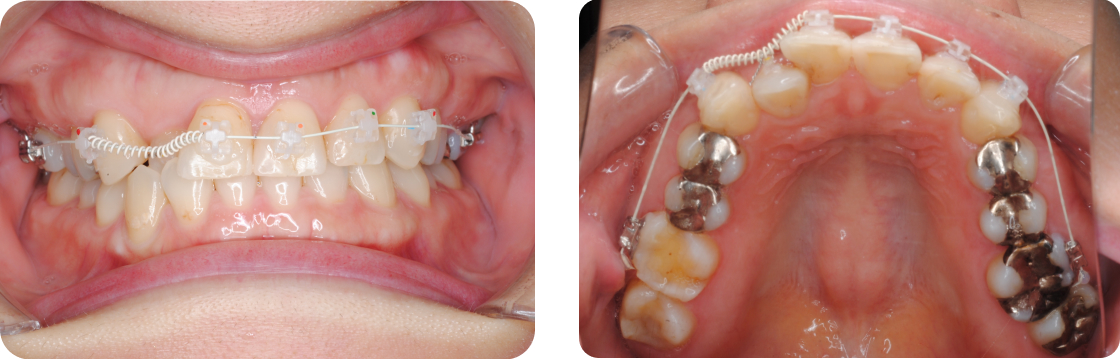

部分矯正で使用する装置の一例(ワイヤー矯正)

上記は前歯の部分矯正装置の画像です。

歯の表側に小さなブラケットを取り付け、そこにワイヤーを通して歯を動かす方法は、昔から多くの症例で使われてきたスタンダードな矯正治療です。

部分矯正では、通常6〜10個程度のブラケットを使用します。これは、全体矯正で使う24個前後のブラケットと比べて、非常にコンパクトな装置です。

見た目に関しては、ブラケット矯正はマウスピース矯正に比べてやや目立つため、見た目を重視する方にはマウスピースが選ばれることもあります。

しかし、ワイヤー矯正の大きなメリットは強い矯正力と細かなコントロール性です。特定の歯を正確に動かしたい場合や、しっかりとした効果を求める方には非常に効果的な方法です。